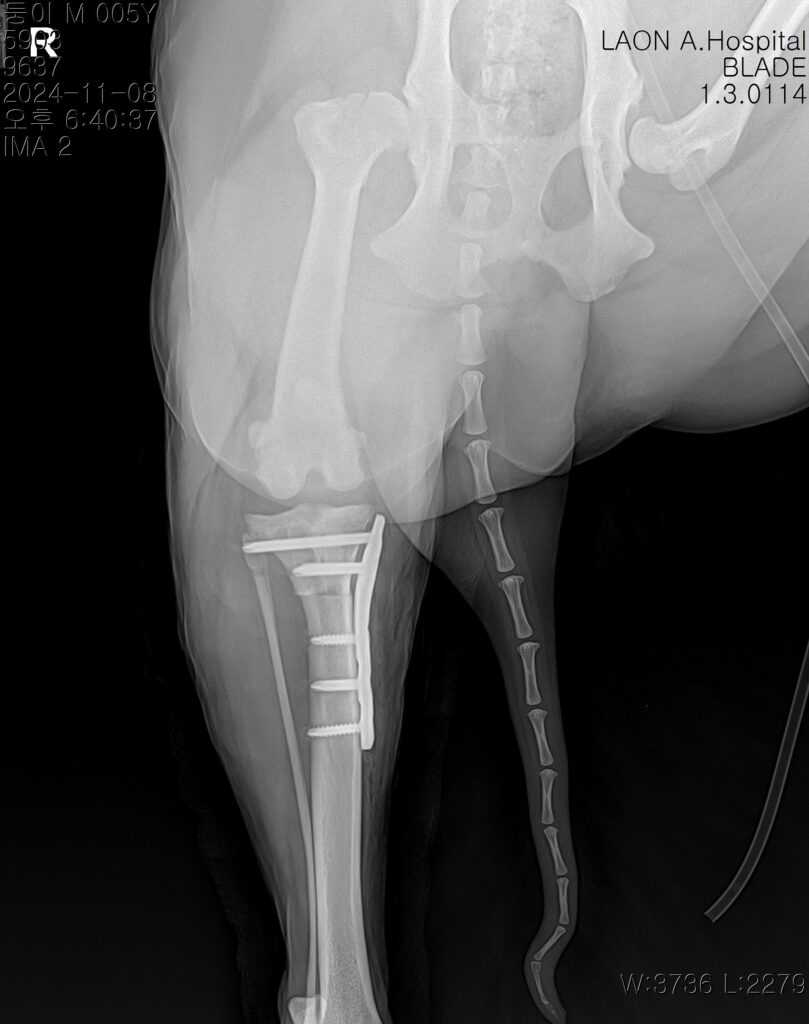

수술사진 / 출처: 라온동물메디컬센터

수술은 마취 안정 하에 무사히 마무리되었고, 절개 부위 봉합 후 감염 방지와 회복을 위한 집중 치료가 이어졌습니다.

수술 후 방사선사진 / 출처: 라온동물메디컬센터